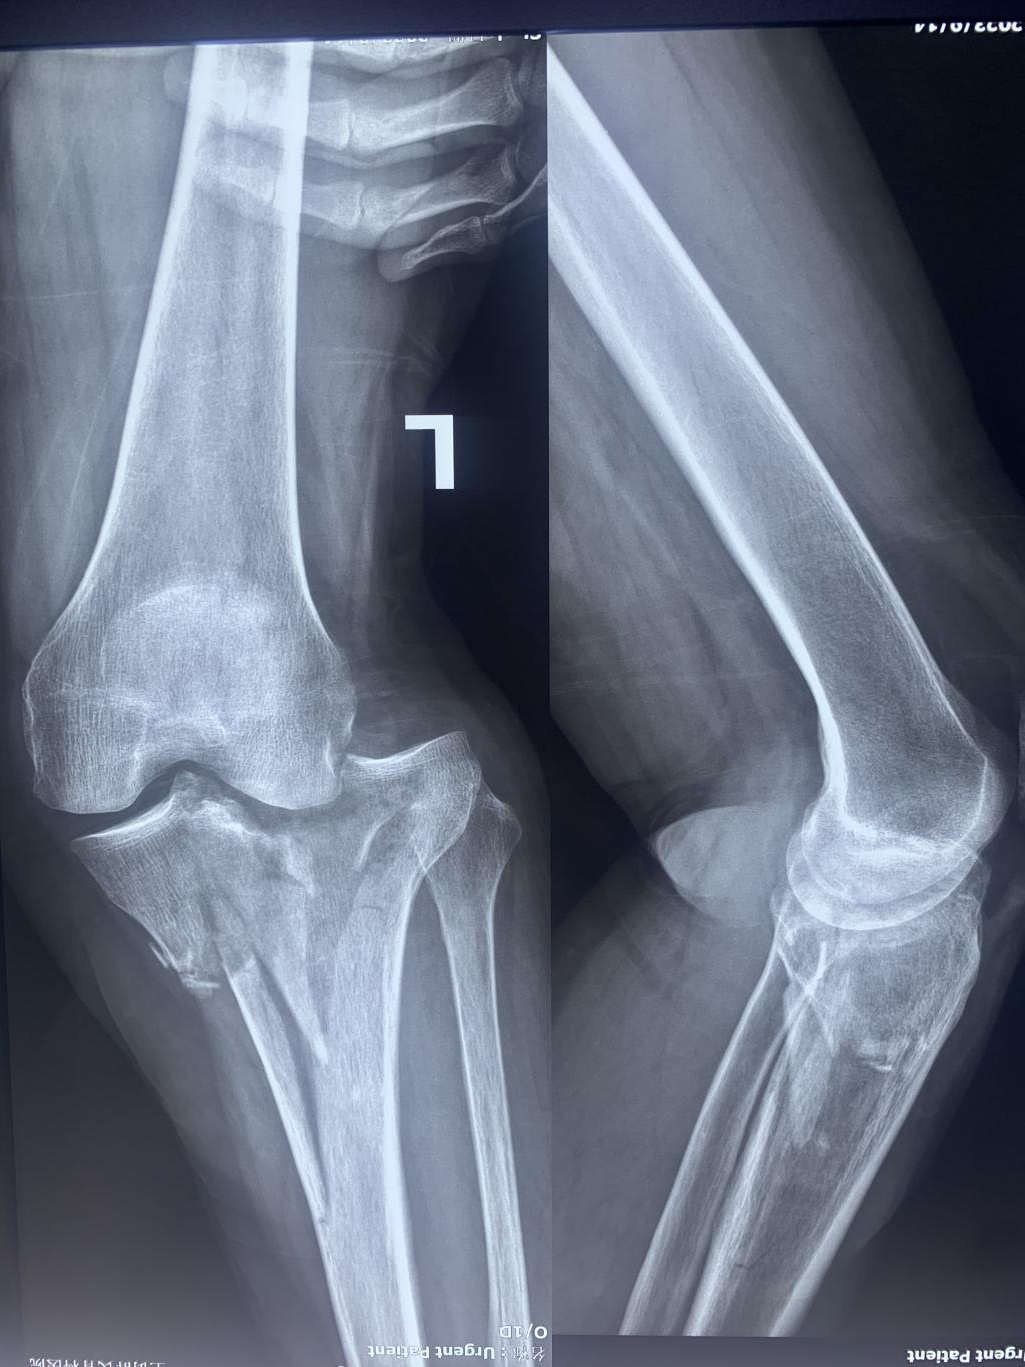

患者:女性,60 歲

以“摔傷左膝關節疼痛、活動受限 2 小時”為主訴于 2023 年 9 月14 日入院。2 小時前工作時不慎滑倒,摔傷左膝關節,被家人送至鄭州市骨科醫院診治。

手術:Schatzker IV型脛骨平臺骨折的手術治療

入院 X 線: